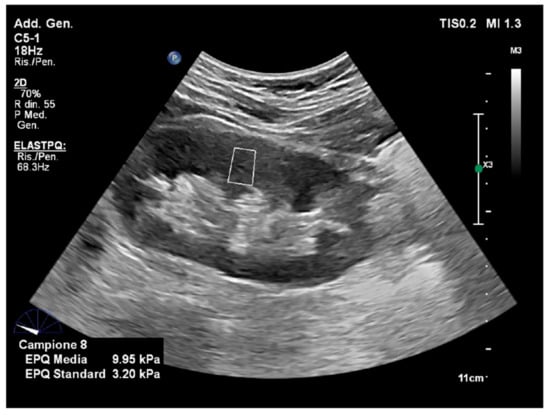

4.1. Liver